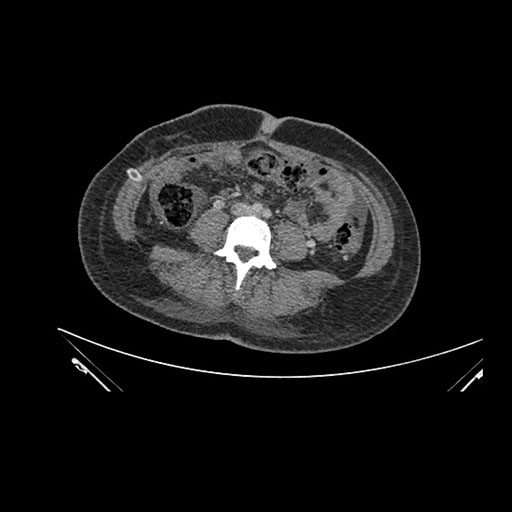

Axial Venous

Imaging analysis

Based on initial findings, which issue(s) would you be most concerned about?